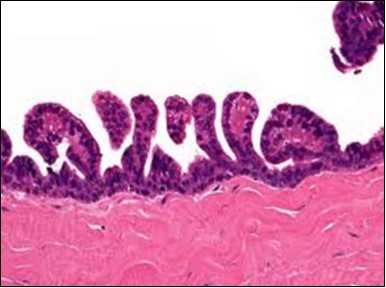

Granular arrangement of malignant cells and intercellular bridges are conspicuous with the demonstration of nuclear atypia, pleomorphism, prominent mitosis and tumour necrosis. A peripheral palisade is discernible within the cellular aggregates. Mitotic figures are common and can be quantified as up to 12 mitosis/ high power field. Tumour differentiation can prominently be of the ductal category with the demonstration of intra-cytoplasmic lumina. Comedo type tumour necrosis is evident along with foci of squamous differentiation The neoplasm is reactive to periodic acid Schiff ‘s (PAS) stain. (Figure 1, Figure 2, Figure 3, Figure 4, Figure 5, Figure 6, Figure 7, Figure 8, Figure 9, Figure 10, Figure 11, Figure 12, Figure 13.

Figure 2.Epidermal projections lined with atypical and malignant epithelial cells in eccrine porocarcinoma (14).